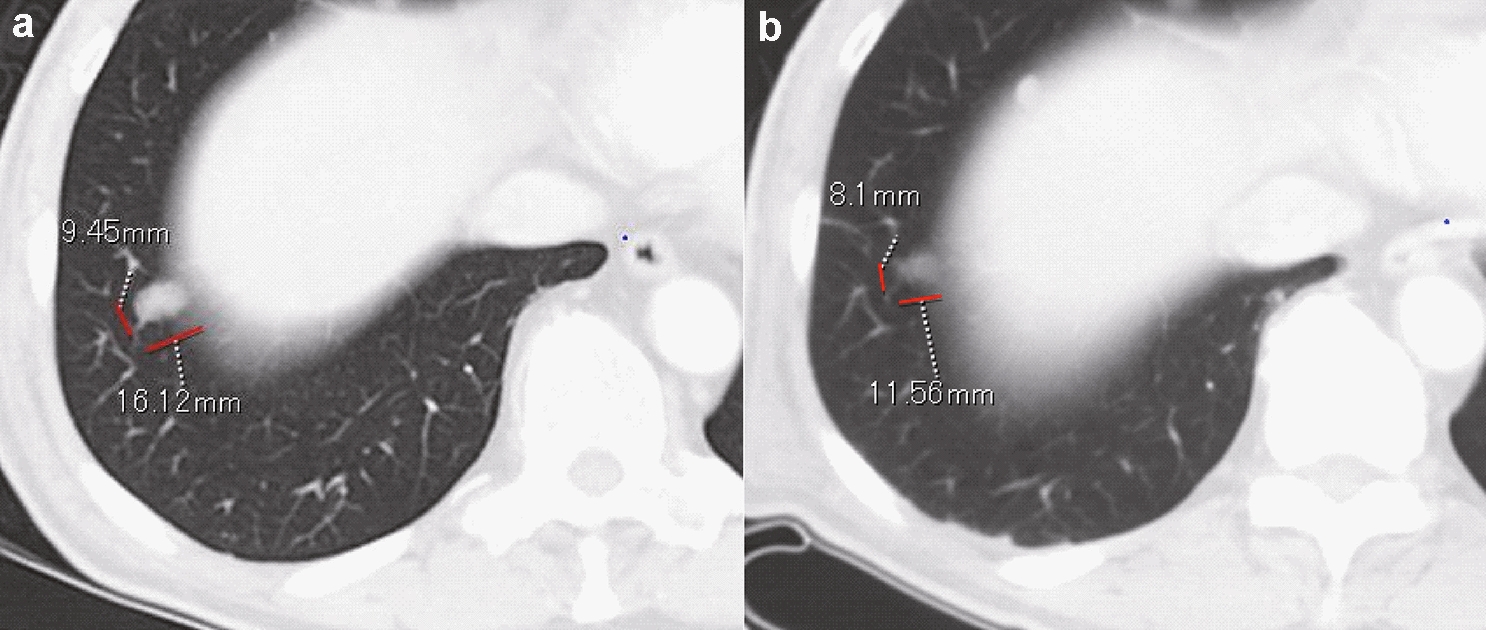

In our evaluation of each target lesion, regression of the tumor was observed at the end of study; a complete response (CR) and PR were observed in 4 of 9 lesions (44%) in the low-dose group and 7 of 9 lesions (77.8%) in the high-dose group (Table 3). In total, 11 of 18 (61%) target lesions showed CR and PR in both groups. The response kinetics in the target lesions in each case was observed at 0 (baseline), 4, and 8 weeks (Fig. 2a-f). Thus, local injection with GEN0101 suppressed tumor growth in patients with melanoma in a dose-dependent manner. Waterfall plots of best overall response recorded for all patients in this clinical trial are shown in Fig. 3. In addition, the solitary lesion in the right pulmonary S9 segment of patient 1 in low-dose group, who had failed prior chemotherapy (Fig. 4a), showed 23.1% shrinkage, which was regarded as stable disease according to RECIST version 1.1 (Fig. 4b).

Fig. 4

The decreased size of lung metastasis after the administration of GEN0101. The solid lesion in the right pulmonary S9 segment detected at baseline a had shrunk at week 8 b

In addition to direct killing, antitumor immunity induced by GEN0101 may be exerted as therapeutic effect. HVJ-E recruits CD8+ T cells at the administration site as well as at the non-administration site to evoke antitumor immunity [9]. Therefore, it is considered that antitumor immunity was also induced by GEN0101 in the present trial; an increase in the NK cell activity and IFN-γ was confirmed (Fig. 5). The NK cell activity increased immediately after the administration of GEN0101, peaking at 6 weeks and followed by a gradual decrease in the low-dose group. This tendency was also seen during clinical studies, suggesting that the NK cell response was transient. There was little change in the NK cell activity in the high-dose group, possibly because of the high level of NK cell activity (about 80%) at baseline. IFN-γ levels increased transiently after six administration sessions at two weeks, which was considered to contribute to the activation of CTL. According to an in vitro study, HVJ-E can induce dendritic cell maturation [4]. Tumor-specific T cells were trained by dendritic cells infiltrated from local tumor [4]. CTL against local tumor antigen was also detected in a mouse malignant melanoma model [6]. Based on these findings, we suspect that activated NK cells and CTLs stimulated by the production of IFN-γ spread to distant metastasis and might have thus contributed to the reduced size of lung metastasis (Figs. 4 and 5). Systemic effects of HVJ-E may be mediated by both innate and adaptive immunity in humans. Therefore, the more potent efficacy may be obtained via combination therapy with an immune checkpoint inhibitor.